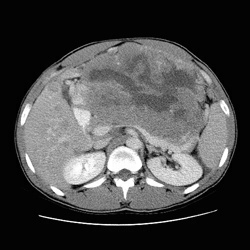

RADIOLOGY: ABDOMEN: Case# 32790: LARGE MASS - NEUROENDOCRINE TUMOR VS SARCOMA. 38 year old male with abdominal pain. Large intraabdominal mass with mesenteric implants and liver metastases has the appearance most consistent with a sarcoma. Due to its large size, it is difficult to determine its point of origin.